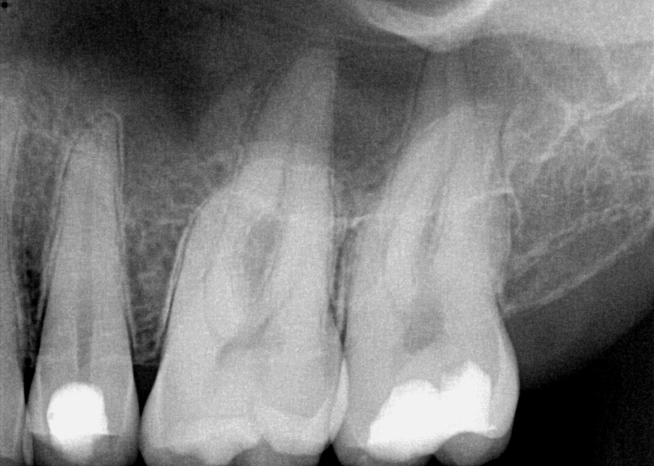

Fig 3. Preoperative maxillary left bicuspid.

Figure 3

The patient presented with temperature sensitivity and pain during mastication (Figure 3). Local anesthesia was delivered, and steps 1 through 4 were performed.